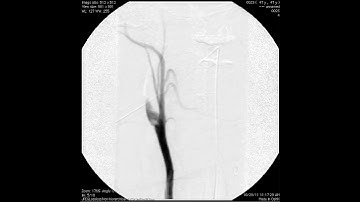

A Spontaneous Basilar Artery Dissection With an Intimal Flap Imaged With Several Techniques